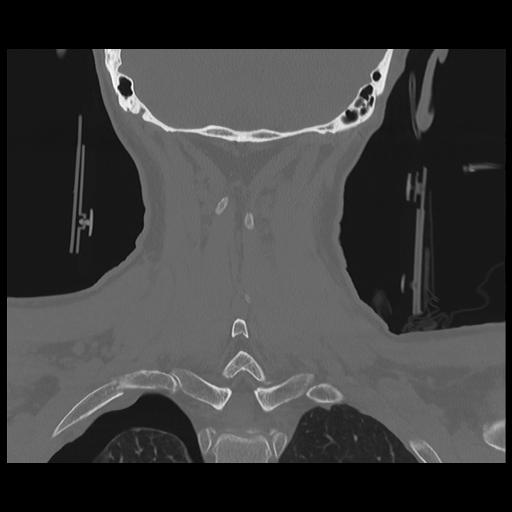

16 HUESO,,Coronal,2.000,HUESO,Coronal,